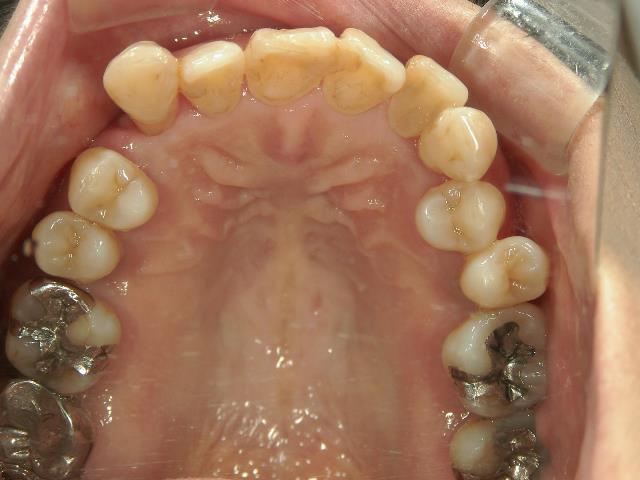

矯正歯科(全顎ワイヤー矯正)治療後

矯正歯科 治療後